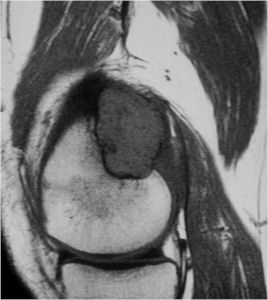

- Also useful in determining extent

- There is often extensive edema around the tumor in the surrounding bone and soft tissues that can lead to a misdiagnosis of a malignant tumor.